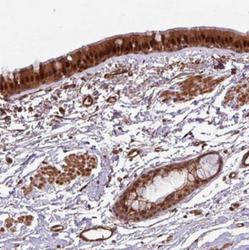

- Main image

- Experimental details

- Immunohistochemistry-Paraffin: C7orf50 Antibody [NBP2-30873] - Staining of human bronchus shows strong cytoplasmic and nuclear positivity in respiratory epithelial cells.